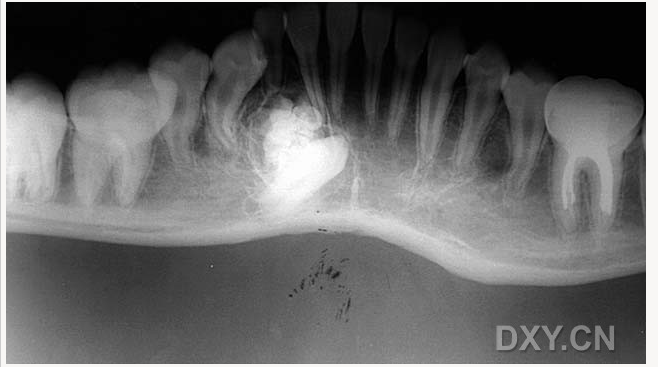

牙源性鈣化囊腫

牙瘤!

牙源性鈣化囊腫    牙瘤!

牙瘤

良性成牙骨質(zhì)細胞瘤